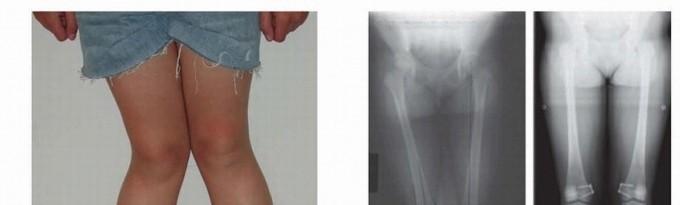

- ###

- FIG 3 • A. A 7-year-old boy with traumatic amputation from a lawn mower injury with varus deformity causing difficulty with prosthetic wear. B,C. Although the CORA was a result of fracture malunion proximal to the distal femoral physis, guided growth was chosen as an alternative to osteotomy to straighten the limb and to improve prosthetic wear.